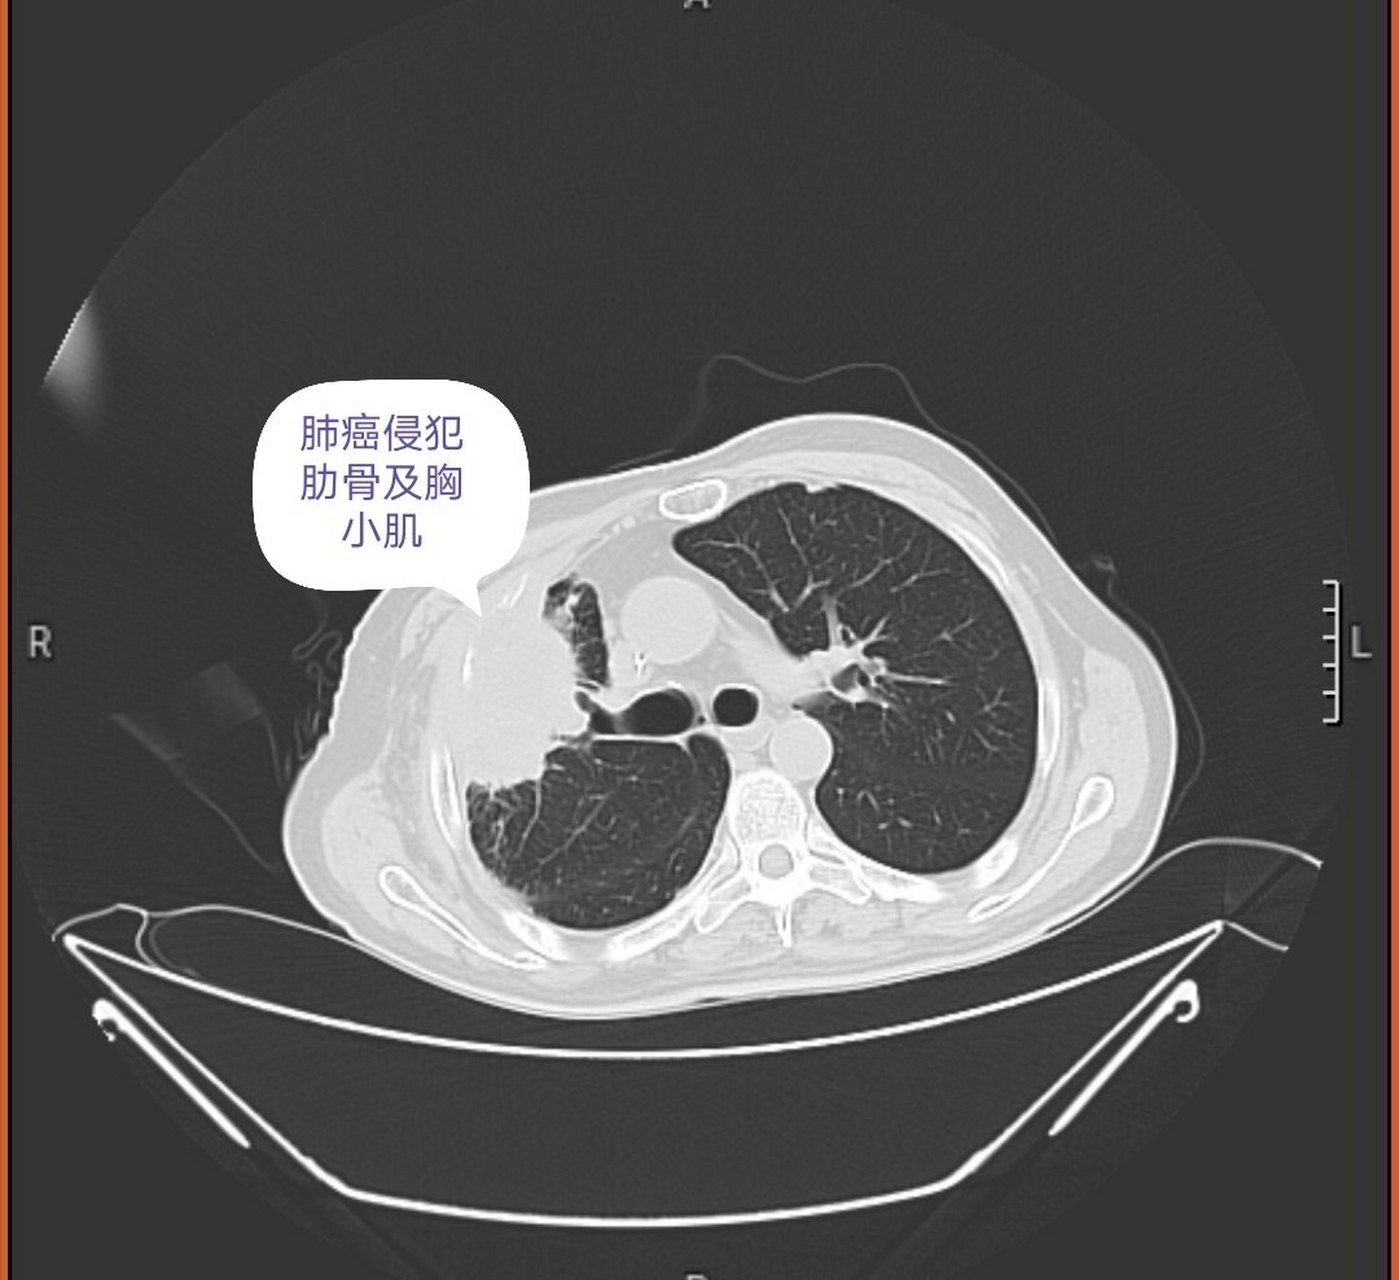

淋巴结转移的局部晚期肺癌(iiia-n2期),治疗该如何排兵布阵?